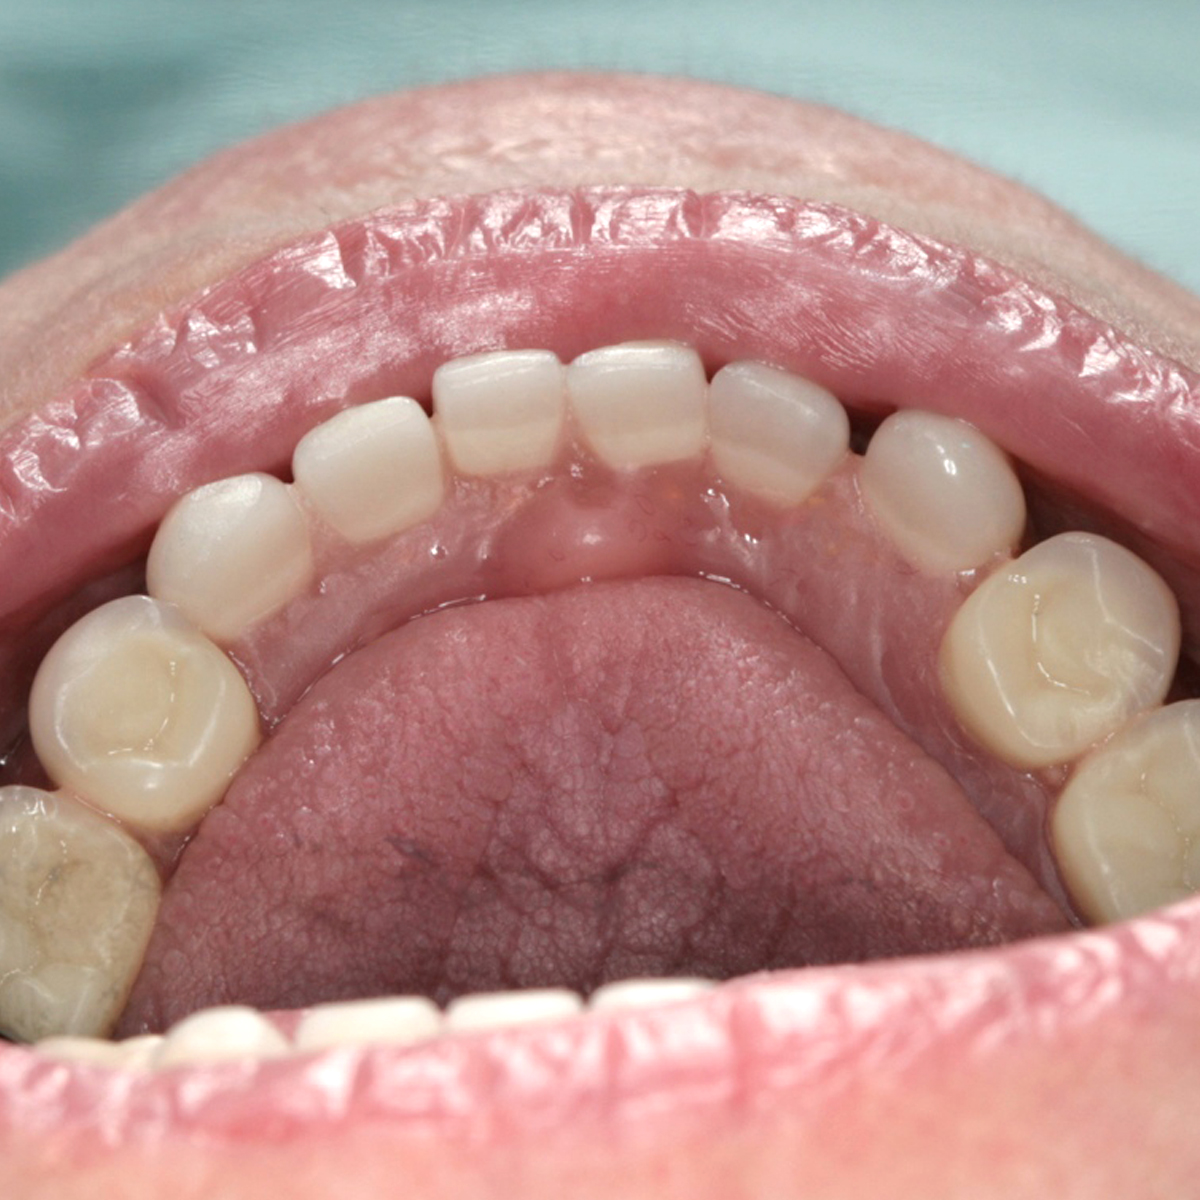

Retracted Tongue Position

Tongue position is important to maintain stability of the lower denture and develop the proper length of the lingual flange.23 Tongue positions may be classified as “normal” or “retracted” (Figure 12).23 A normally positioned tongue completely fills the floor of the mouth. The lateral borders rest over the posterior edentulous ridges, where they would normally rest over the occlusal surface of the posterior teeth, and the tip of the tongue rests on or is just lingual to the anterior ridge crest. This tongue position maintains the correct position of the floor of the mouth. Retracted tongue posture is demonstrated when the tongue is pulled back, exposing the floor of the mouth, and the lateral borders are either medial to or posterior to the edentulous ridge. In addition, the tip of the tongue is located in the posterior portion of the mouth or is withdrawn into the body of the tongue itself. Approximately 35% of patients present with retracted tongue posture.23 The prognosis of patients with a retracted tongue can be improved by making them aware of their condition and instructing them to position the tongue correctly during rest and function. Prescribing tongue exercises23 and placing a training bead of resin on the lingual aspect of the denture in between the central incisors24 can also help retrain the tongue and maintain its proper position (Figure 13 and Figure 14).

(12.) Retracted tongue position.

Figure 12